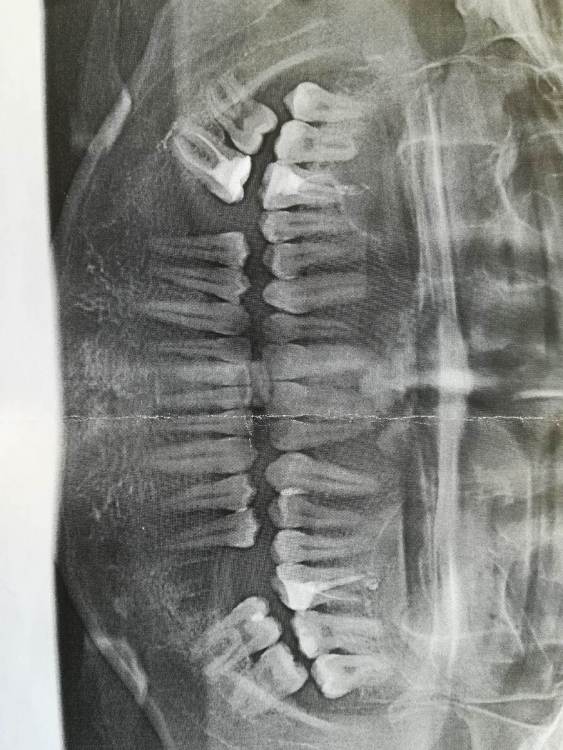

Nik-E Опубликовано 11 октября, 2021 Поделиться Опубликовано 11 октября, 2021 Здравствуйте. Нужно мнение специалистов. Была проведена имплантация, сделан снимок, на снимке непонятное пятно как будто похожее на резьбу, до установки импланта такого пятна не было. Что это за пятно может быть? И правильно ли установлен имплант? Заранее спасибо. На снимке я место с пятном выделил. Ссылка на комментарий